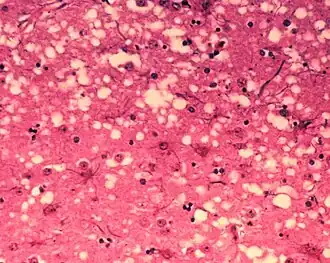

Brain tissue of a cow with BSE showing the typical microscopic "holes" in the grey matter

Diagnosis of BSE continues to be a practical problem. It has an incubation period of months to years, during which no signs are noticed, though the pathway of converting the normal brain prion protein (PrP) into the toxic, disease-related PrPSc form has started. At present, no way is known to detect PrPSc reliably except by examining post mortem brain tissue using neuropathological and immunohistochemical methods. Accumulation of the abnormally folded PrPSc form of PrP is a characteristic of the disease, but it is present at very low levels in easily accessible body fluids such as blood or urine. Researchers have tried to develop methods to measure PrPSc, but no methods for use in materials such as blood have been accepted fully.

The traditional method of diagnosis relies on histopathological examination of the medulla oblongata of the brain, and other tissues, post mortem. Immunohistochemistry can be used to demonstrate prion protein accumulation.[26]